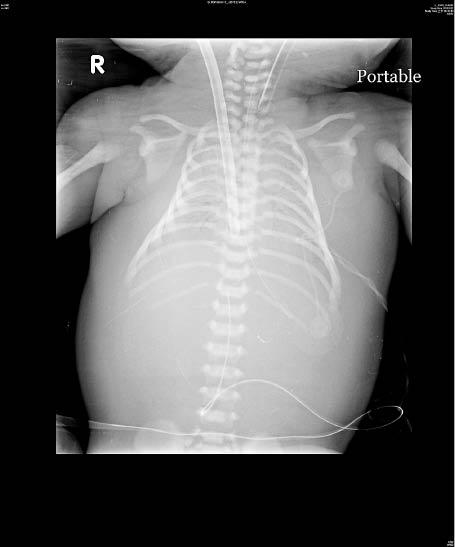

高雄長庚兒童內科主治醫師林盈瑞表示,男嬰轉到兒內加護病房時,其血氧濃度仍僅50%,X光檢查肺部兩側發炎,合併出現呼吸急促、心跳變慢等症狀,診斷為「胎便吸入症候群」,亦即胎兒因過期妊娠、窘迫等問題,在子宮內解出大便於羊水中,且把胎便吸入肺部,引起肺部發炎及破壞。